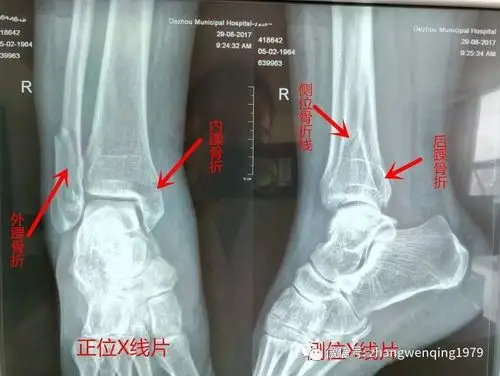

踝关节骨折不是打石膏那么简单